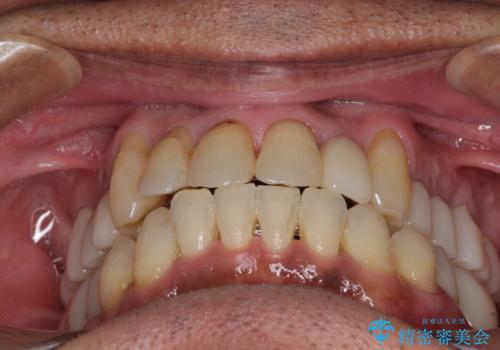

- 前歯がのデコボコや、奥歯に咬んだときに痛みがあるとのことで来院された患者様です。

全体的に問題が多く、全てをしっかりと治療したいとのことでした。

全体的に中等度の歯周病と診断されたため、歯周外科処置やインプラントによる咬合回復から進めて行き、矯正治療による歯列改善を行った後にオールセラミッククラウンにて補綴することとしました。